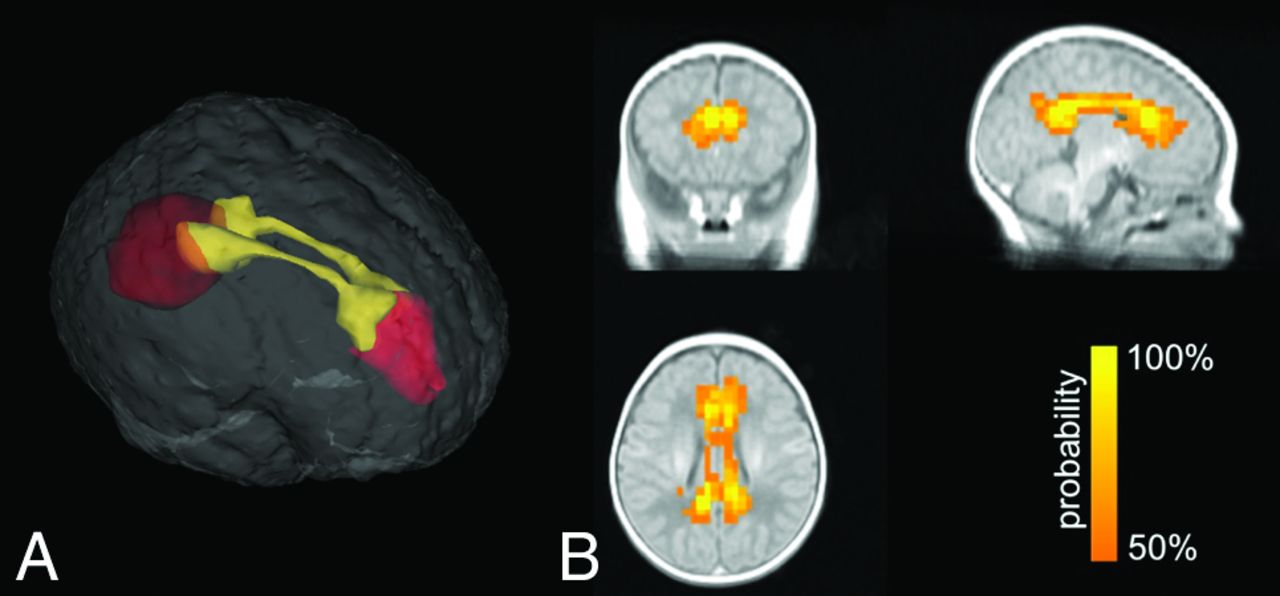

As shown in Fig 2, the bilateral cingulum bundles, which are the primary fiber tracts connecting the medial prefrontal cortex and the posterior cingulate cortex/precuneus, were reconstructed. Figure 3 shows the group comparison in DTI metrics of the reconstructed cingula. The FA values in the BI group (0.20 ± 0.03) were significantly lower than those in the control group (0.25 ± 0.03, F = 26.79, P < .001). The MD and RD values were both elevated in the BI group (MD, 1.32 ± 0.17; RD, 1.24 ± 0.16) compared with the control group (MD, 1.19 ± 0.16; F = 6.44, P = .015; RD, 1.06 ± 0.16; F = 13.35, P = .001). No significant difference was found in AD between the 2 groups (BI, 1.47 ± 0.19; control, 1.44 ± 0.18; F = 0.12, P = .731).

Group tract map of the reconstructed cingula. Each voxel value represents the probability that subjects had some cingula in it.